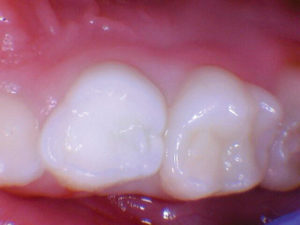

Caso 1

Un paciente de 8 años presentó descomposición de OD en un primer molar primario con síntomas de pulpitis reversible. El diente fue el tratamiento planificado para una restauración de OD con Activa Bioactive Restorative (Pulpdent). Tras la excavación por descomposición, se produjo una exposición pulpar que requirió una pulpotomía terapéutica. Debido a la edad del paciente, me sentí cómodo con una pulpotomía terapéutica con Biodentine (Septodont) seguida de una restauración estética. Si el paciente hubiera tenido entre cuatro y cinco años, me habría restaurado con una corona de acero inoxidable debido a su historial comprobado de longevidad.

Figura 1 Vista preoperatoria del primer molar primario superior. |